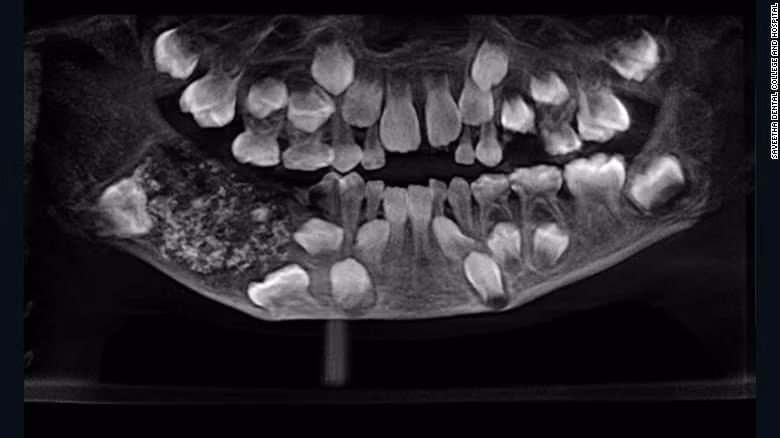

Khi bác sĩ chụp X-quang miệng cậu bé, họ phát hiện một phần rỗng ở hàm dưới chứa hàng trăm chiếc răng bất thường, theo bác sĩ Prathiba Ramani, trưởng khoa Răng miệng tại bệnh viện Saveetha.

"Tổng cộng khoảng 526 chiếc răng kích thước từ 0,1 mm tới 15 mm ở trong miệng cậu bé. Thậm chí, chiếc nhỏ nhất cũng có đầy đủ thân, chân và men răng", bác sĩ Ramani cho hay.